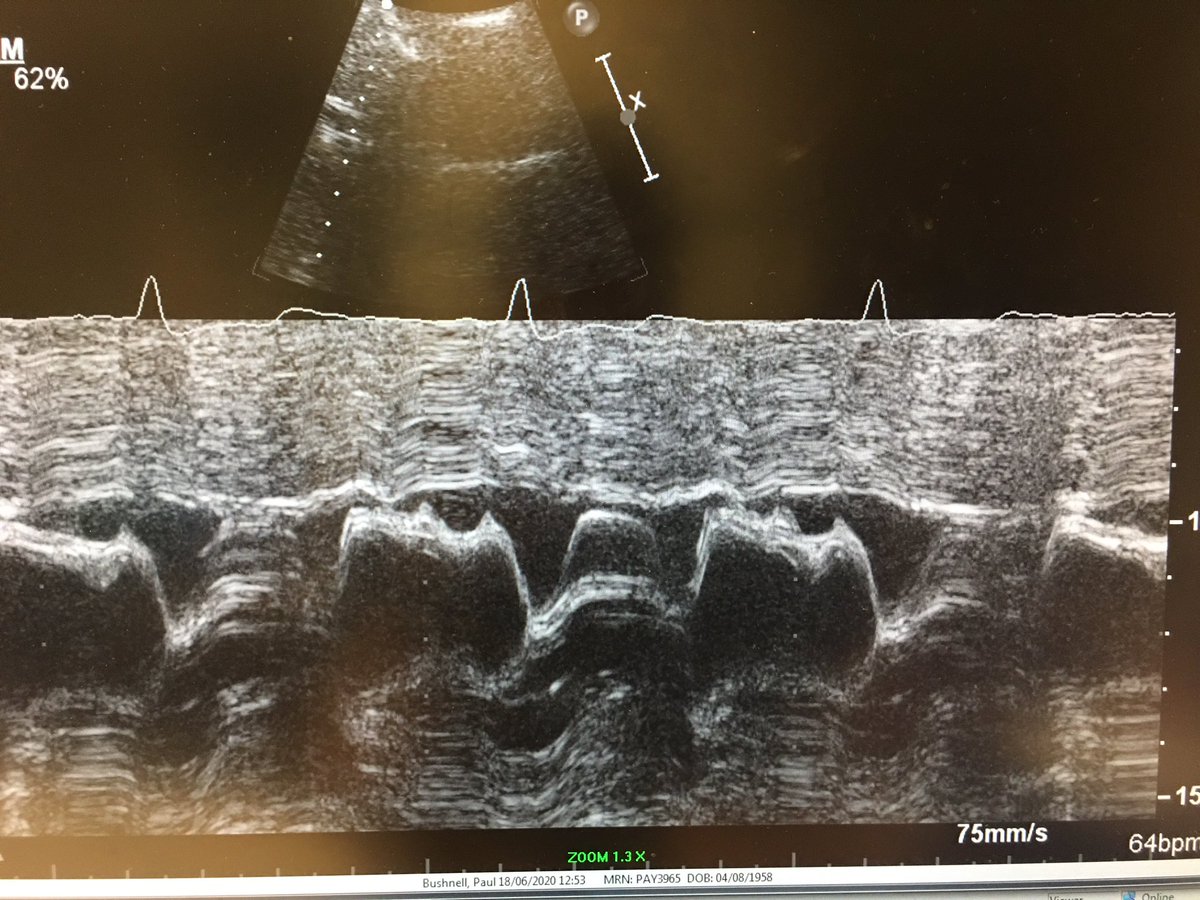

6) and because I’m old I did a couple of m-modes - one to show the systolic anterior motion (SAM) and the early closure of the aortic valve. #HOCM